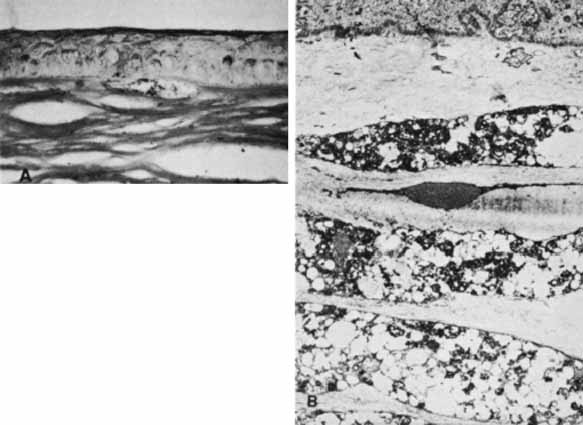

With time, a fresh endothelium will resurface the posterior cornea and synthesize a new basement membrane, filling the dehiscence and accentuating the edges of the tear. After the corneal edema resolves, the edges of the break will appear as rounded, glassy ridges protruding from the posterior cornea readily apparent under retroillumination. In some instances, one edge of the tear may separate from the stroma and hang into the anterior chamber as a falciform ledge, with its free edge curling anterior to form a scroll (Fig. 9). When two tears occur parallel to each other, the edge of Descemet's membrane between the tears may curl toward each other. This strip of Descemet's may then disassociate from the overlying stroma, resulting in a glassy strand across the concavity of the posterior cornea. In this circumstance, the newly laid basement membrane will have a beaten-metal, guttate appearance.

Fig. 9 Histopathology of healed tears in Descemet's membrane from congenital glaucoma. A. Regenerating corneal endothelium has produced new basement membrane in the bed of the tear and over each edge (arrows) of the tear. B. Main figure demonstrates one edge of the tear in Descemet's membrane, which has separated from the overlying stroma and coiled anteriorly like a watch spring. Regenerated basement membrane has encased this and formed a prominent ledge. Inset. Other edge of the tear, in which regenerated basement membrane forms a ridge protruding into the anterior chamber. (Waring GO, Laibson PR, Rodrigues MM: Clinical and pathologic alterations of Descemet's membrane: With emphasis on endothelial metaplasia. Surv Ophthalmol 18:325, 1974)

Histopathologically, the edge of a Descemet tear curls toward the stroma, possibly because of the differential elasticity between the anterior banded and posterior nonbanded layers within Descemet's membrane.67 As the new regenerating endothelium spreads over the edge, it encases the original coiled Descemet's membrane in a thick multilaminar periodic acid-Schiff (PAS)-positive basement membrane (Fig. 9). This new basement membrane forms the clinically evident refractile edge. Within the bed of the tear, the regenerating endothelium lays down an irregular basement membrane with focal excrescences that produce the beaten-metal appearance.

Ultrastructural studies of the cornea in human congenital glaucoma are rare,68 but the ultrastructure in rabbits with spontaneous buphthalmos has been described in detail.69 Intraepithelial and subepithelial edema is present, accounting for the ease with which one can remove the epithelium clinically. Stromal edema, loss of regular collagen architecture, and the degree of scarring correlate with the degree of corneal opacity and thickness. In rabbits with mild to moderate corneal clouding, Descemet's membrane is thicker than normal and manifests the compact structure typical of basement membrane. In rabbits with more severe corneal opacification, a layer of small-diameter collagen fibrils enmeshed in amorphous material appears posterior to Descemet's membrane. In these rabbits, no tears in Descemet's membrane are observed clinically or histopathologically, suggesting that corneal edema may occur from elevated intraocular pressure alone. The thin endothelial cells can be as large as four times their normal size and contain cytoplasmic vacuoles appearing as small pits on scanning electron microscopy. In humans, these enlarged endothelial cells may represent the ones that decompensate later to produce corneal edema. Recently, in vivo confocal microscopy has been used to further evaluate Descemet's tears and endothelial changes associated with congenital glaucoma.70 Key findings include a mild reduction of keratocyte density in the middle and posterior stroma, along with the presence of discontinuous hyperreflective structures overhanging the endothelial layer at the level of Descemet's membrane. Additional confocal analysis of the endothelial layer demonstrate a low cell count, focal cellular lesions, severe polymegethism, and pleomorphism.70